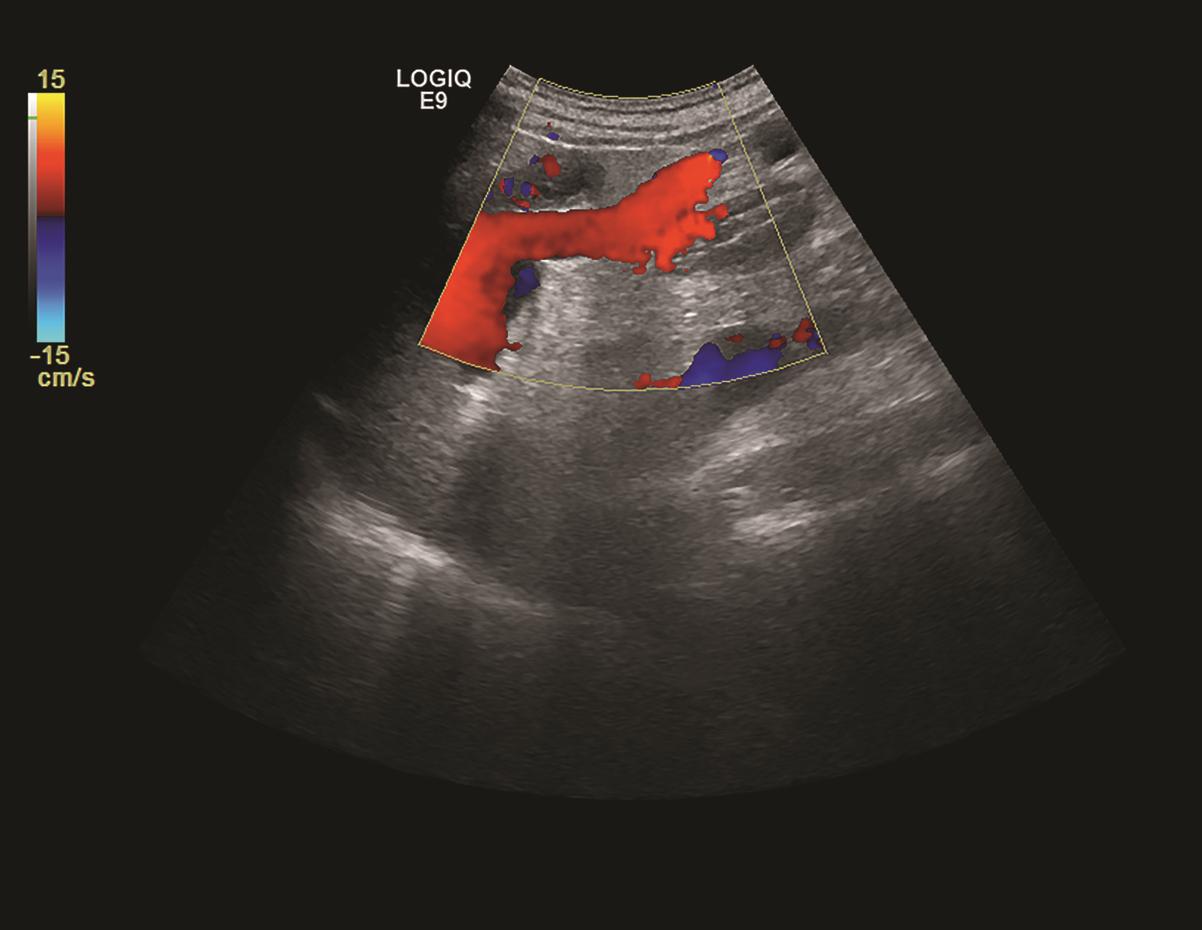

肝移植术后自发性肝破裂出血1例报告

马健, 何力宏, 王凌云, 翟亚楠, 李汛, 张磊

2022, 38(4): 891-893. DOI: 10.3969/j.issn.1001-5256.2022.04.030

摘要(1066) HTML (365) PDF (3041KB)(58)

摘要: